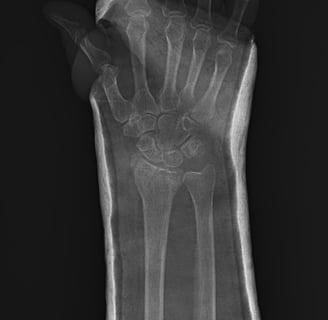

Fracturas y Luxaciones

Atención rápida y efectiva para lesiones agudas.

Le ofrecemos atención especializada en Traumatología y Ortopedia, brindando confianza y seguridad en momentos de emergencia para lesiones músculo esqueléticas como fracturas, luxaciones o lesiones articulares.

Atención de emergencias en lesiones músculo esqueléticas, fracturas y luxaciones con confianza y profesionalismo.